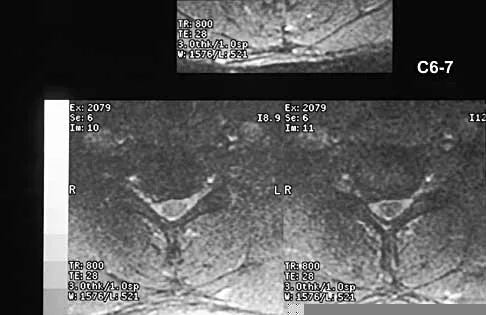

A 40-year-old carpenter has a 3-month history of right arm pain and neck pain that now leaves him unable to work. Examination reveals a positive Spurling test, weakness of the biceps, and a mildly positive Hoffman's sign on the right side. Electromyography and nerve conduction velocity studies show a right C6 deficit. Figures 27a through 27c show MRI scans that reveal two-level spondylotic disease at C5-6 and C6-7, a large herniated nucleus pulposus at C5-6, and a prominent ridge and hard disk at C6-7. Nonsurgical management fails to provide relief, so the patient elects surgical intervention. Which of the following surgical options would give the best long-term results?

The patient has a single-level deficit by clinical examination but an adjacent level that may be pathologic. Hilibrand and associates, in a review of 374 patients with myeloradiculopathy treated with single-level or multilevel anterior cervical diskectomy and fusion, showed that 25% of patients had an occurrence of new radiculopathy or myelopathy at an adjacent level within 10 years after surgery. Reoperation rates were highest in those patients where the adjacent nonfused segment was C5-6 or C6-7. Those patients who had multilevel fusions had a lower incidence of adjacent segment disease. The authors recommended incorporating an adjacent level in the initial procedure in patients with myelopathy or radiculopathy when significant disease was noted. Posterior keyhole foraminotomy is an excellent procedure for single-level radiculopathy but is not effective in relieving myelopathy. Anterior cervical diskectomy without fusion has an increased incidence of hypermobility and neck pain on long-term follow-up. In a later review, these authors reported improved fusion rates and better clinical outcomes with the use of strut fusions instead of multilevel interbody grafts. Hilibrand AS, Carlson GD, Palumbo MA, Jones PK, Bohlman HH: Radiculopathy and myelopathy at segments adjacent to the site of a previous anterior cervical arthrodesis. J Bone Joint Surg Am 1999;81:519-528. Henderson CM, Hennessy RG, Shuey HM Jr, Shackelford EG: Posterior-lateral foraminotomy as an exclusive operative technique for cervical radiculopathy: A review of 846 consecutively operated cases. Neurosurgery 1983;13:504-512.